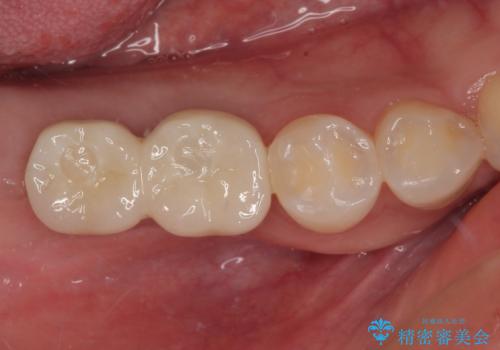

その後、挺出していた右上第一大臼歯と第二大臼歯に装着されていた銀歯についても、審美性と適合性の向上を目的に、オールセラミッククラウンにやり替えました。

これにより、より自然で美しい見た目と、高い精度の咬合が得られています。